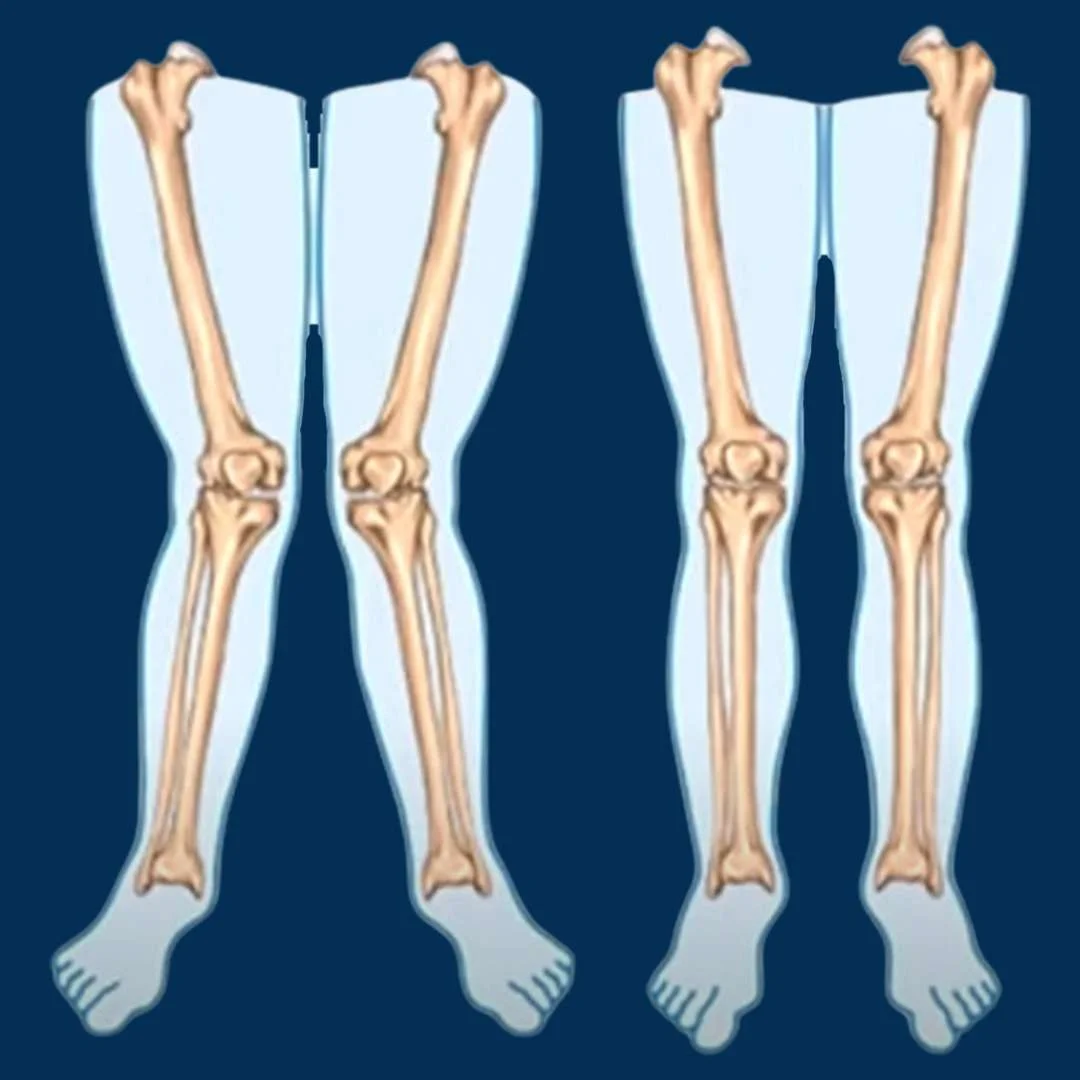

Bowleg Deformity

Bowleg deformity, also known as genu varum, is ...

Knock Knee Deformity

Knock knee deformity, or genu valgum, is a cond...